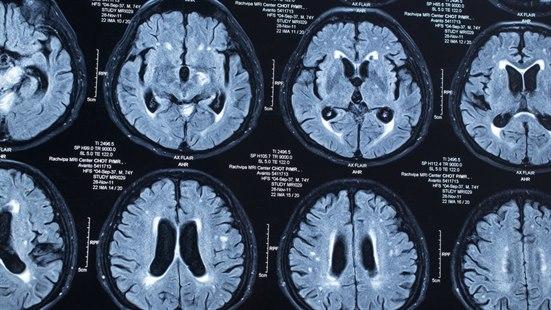

Allmennlegen mistenkte en sentralnervøs nevrologisk tilstand og henviste mannen til MR av hjernen. Noen dager senere forelå svaret. Det var multiple lesjoner spredt rundt i bakre skallegrop, blant annet i hjernestammen, cerebellum og i hypothalamus. De romoppfyllende prossesene ga et økt intrakranielt trykk, og hodepinen ble vurdert som truende herniering. Han ble umiddelbart innlagt nevrologisk avdeling, og det ble startet høydosebehandling med steroider for å få ned det intrakranielle trykket.